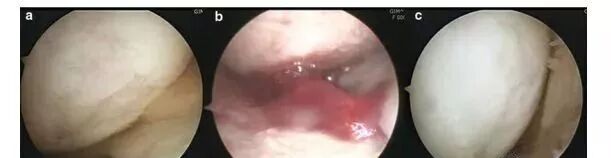

上海本正干细胞技术有限公司提供的干细胞是从脐带、胎盘中提取的一种修复器官机理的未完全分化的原始细胞,具有自我更新、多项分化和高度繁殖的能力,医学上称为“万能细胞”,它是形成人体各种组织器官的起源细胞。干细胞对临床上一些疑难疾病的治疗如:脑瘫、老年痴呆、脑萎缩、帕金森病、中风、肝硬化、糖尿病、红斑狼疮、股骨头坏死、软骨和关节损伤、心脏和脊髓损伤等,取得显著效果,它拥有更加鲜活细胞能量,可以快速、有效进入体内,分泌多种有益细胞因子,调节体内微环境,激活干细胞再生能力,重启时光之门,追溯青春绽放源头,实现对人体衰老状态减缓,同时有效改善身体亚健康以及预防肿瘤发生。